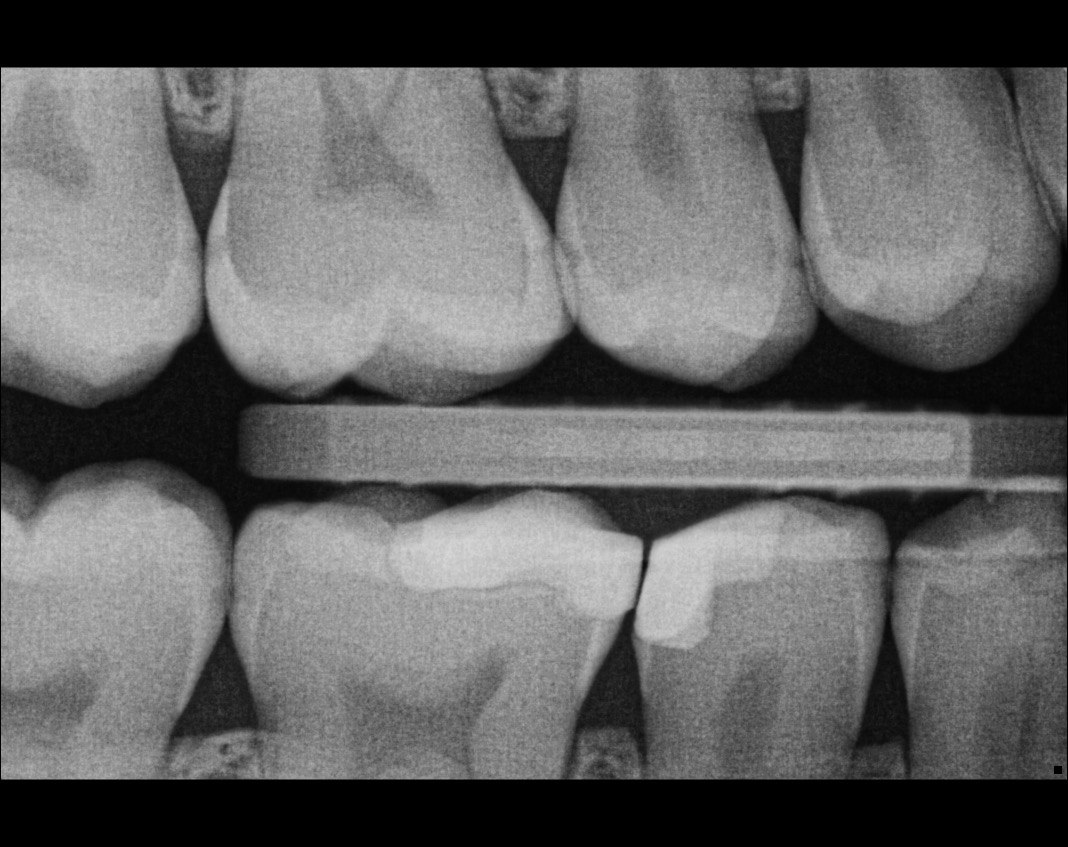

Question 16: Which surface shows overhang?

Question 17: Which surface shows overhang?

Question 18: Which surface shows overhang?

Question 19: Which option can be chosen for the tooth # 3.6?

Question 20: which tooth shows defective resotration?